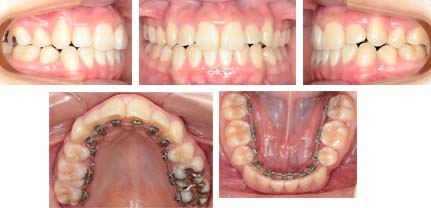

来院時の写真

上顎の側方歯間の幅が狭く、側切歯(2番目の前歯)、犬歯が内側に入って反対咬合になっています。下の歯にはそれほどでこぼこがありませんがタイトルに記載させて頂いたように骨格性には反対咬合の傾向があります。そのため舌のポジションが低位舌(ていいぜつ)です。低位舌は舌の安静位が下顎の歯列弓の中におかれています。舌が内側から押すために下顎歯列が拡大しやすく下顎前歯は前傾します。これは残念ですが小臼歯を抜いて治療しないと口もとが飛び出してしまい前歯の反対を治す事が出来ません。

治療中の写真

後もう少し噛ませることができれば装置が外れます。治療は成功したと思います。

真ん中もぴったり合っています。患者様も喜んでくれました。

今回もアイ矯正歯科クリニックではアンカースクリュウは使用していません。外科処置は行っていません。表側にはまったく装置は装着していません。